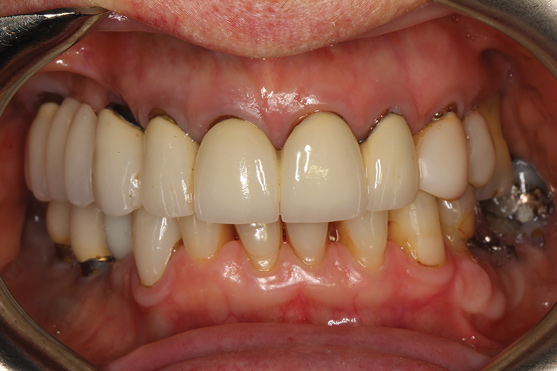

The rigidly fixated provisional was left undisturbed for a minimum of 5 months to allow for osseointegration of the implants. The patient was advised to maintain a soft diet during that time. To prevent fracture of the provisional, cantilevers should be eliminated or minimized and any metal inserts should have at least 4 mm of thickness around them. If any fractures or chips have occurred on the provisional they can be repaired intraorally or extraorally with standard light-cured bisphenol A-glycidyl methacrylate (bis-GMA) or bisacryl composite resins. Figure 14 and Figure 15 illustrate the in-house 3D-printed provisional at 5 months with excellent bone levels on the implants.

Fig 14. Patient’s smile 5 months post-surgery.

Figure 14